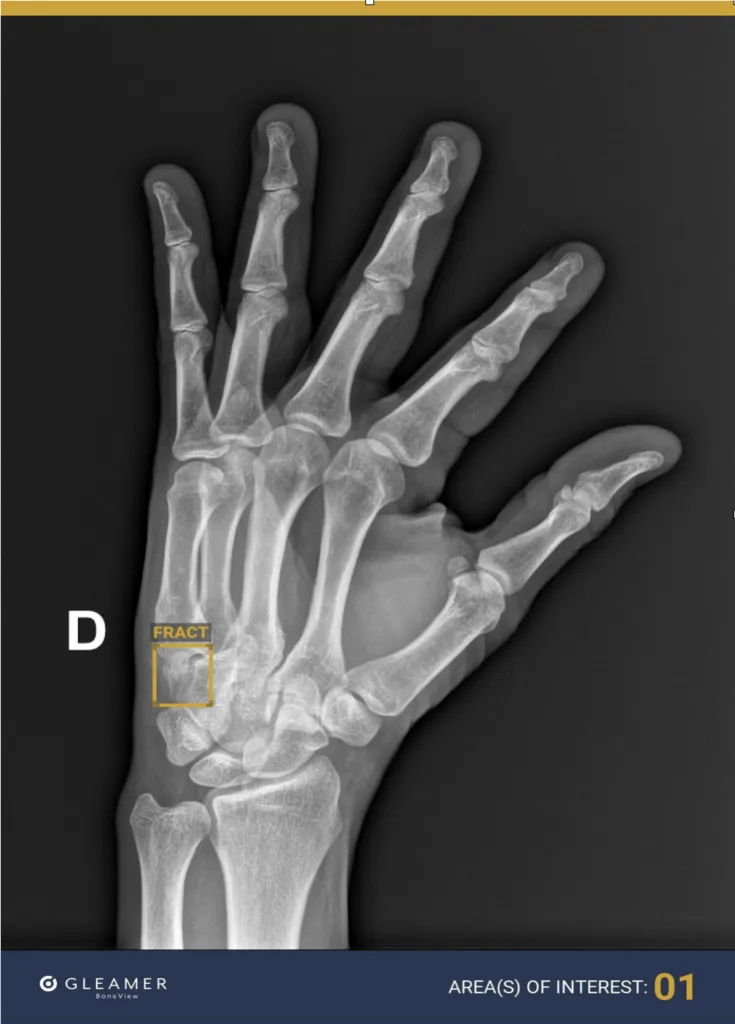

AI in Fracture Care - Bone Break Busters

AI revolutionizes fracture management by enhancing detection, classification, and assessment.

- Fracture Detection & Assessment:

- Identifies occult & stress fractures (e.g., scaphoid, hip, rib) on X-ray & CT.

- AI significantly improves fracture detection, especially occult fractures, on radiographs and CT.